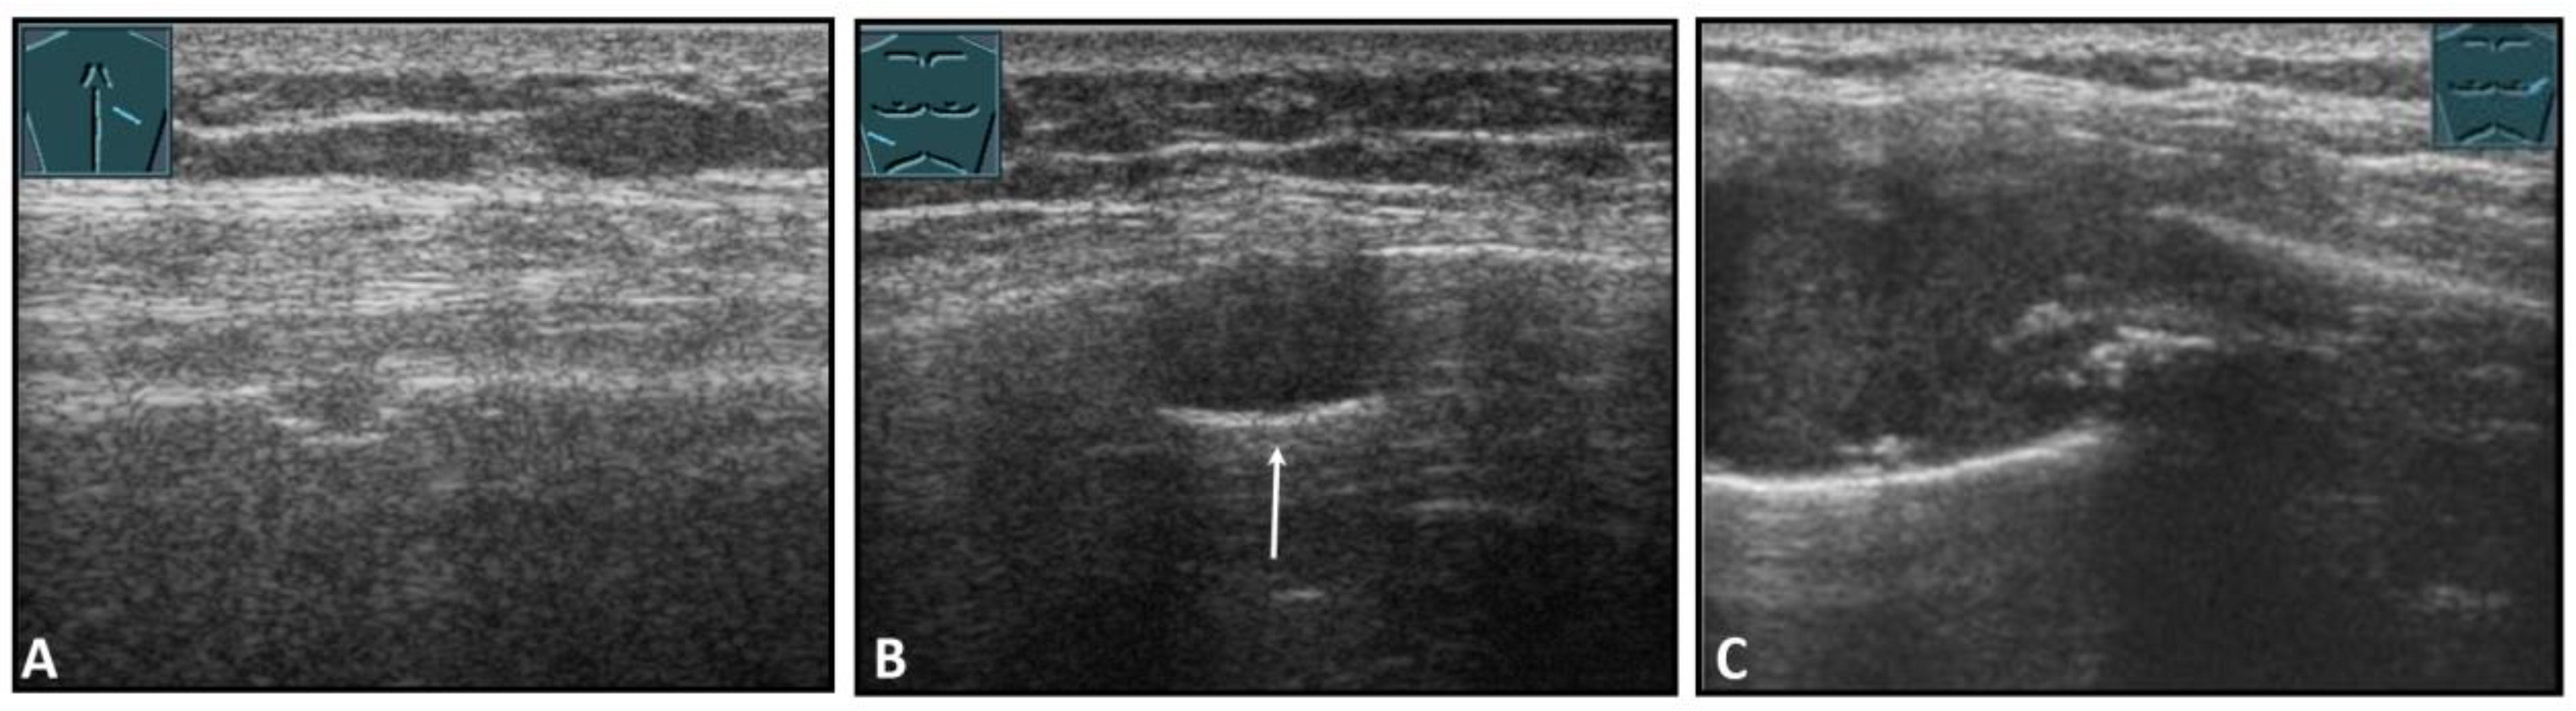

Fractures of ribs or the sternum can be diagnosed by visualizing an interruption of the cortical bone contour. Frequently, a step formation with a surrounding hematoma is found, which is visualized as a blurred-bounded, inhomogeneous, hypoechoic structure (Figure 4). Imaging of reparative processes and contusions is possible. In principle, traumatic fractures cannot be differentiated from pathological fractures unless a tumor soft tissue mantle can be visualized.

Figure 4.

Illustration of different patterns of traumatic rib fractures: (A) major step formation with hematoma (arrow); (B) minor step formation; (C) minimal contour disruption (arrow) with small hematoma; (D) small impression (arrow) with hematoma; and (E) long-standing fractures with bone consolidation.